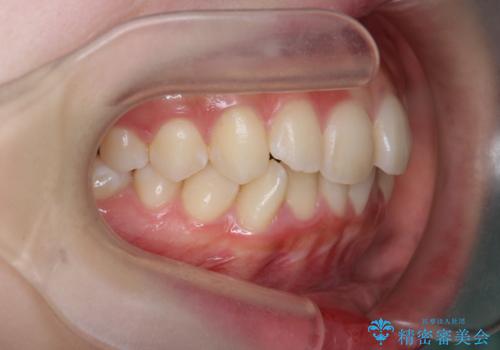

インビザラインライトで行う短期マウスピース矯正治療

- 前歯のガタつきを並べたいたいと、矯正治療を希望され来院されました。

とにかく短期間で前歯だけの治療を行いという希望が強く、全体矯正と前歯だけの部分矯正の仕上がりのイメージを確認したのち14枚のマウスピースで前歯のみの矯正治療を行っていくこととしました。

インビザラインライトは軽度なガタつきや傾斜の改善に用いられる全14枚のマウスピース矯正です。